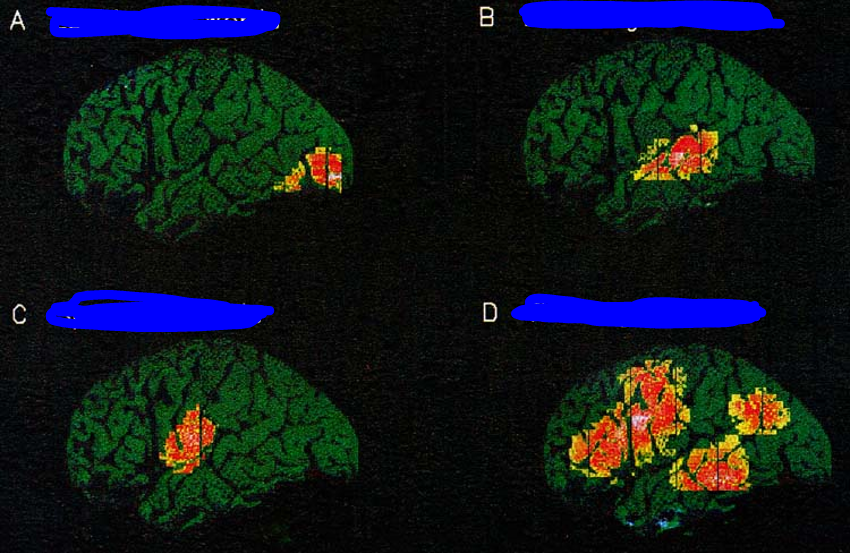

what does the visual hemifield MAPs in the banks of the calcarine sulcus look like

is distorted, many neurons in the posterior half of the cortex process sensory info coming from a small part of the central retina (fovea, macula), with relatively few neuros at the anterior end of the cortex, devoted to processing info coming from a bigger region of the peripheral retina

How is the visual map in the primary visual cortex (V1) organized?

The visual map in V1 is inverted and distorted, with large areas devoted to central vision and smaller areas for peripheral vision